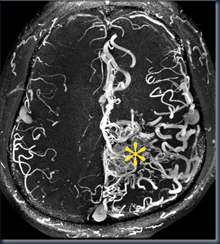

(Bayi normal dan dengan hidrosefalus)--------gambaran otaknya---------------->

---------gambaran CT Scan kepala -------->

(pada dasarnya gambaran pembesarn ventrikel pada bayi dan orang dewasa sama,

pembesaran ventrikel ditegakkan apabila lebarnya lebih dari 7 mm)